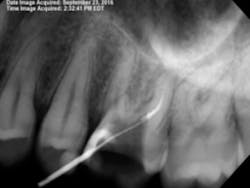

By 2:22 p.m., I was taking periapical x-rays with the gutta-percha to check my working lengths and evaluate the separated files. The x-ray showed that my access wasn’t as open as I originally thought it to be. The canal curved in two places, which caused the file separations. At this point I had two separated files—the 0.1 Twisted File (TF) file and the 15 mm hand file I had used to bypass the canal.

I proceeded to bypass the separated files with a 10 c-file. The apex locator still wasn’t giving me a reading. I was ready to obturate the canal, leaving all the extra metal as fill. Upon drying the canal with paper points, I noticed the paper point disappeared immediately toward the buccal. I took a step back to remove the buccal wall for better access. At this point, I was able to visualize the DB canal much better and was able to remove both of the separated instruments.

After obturation, it became apparent why the apex locator had given no reading for the DB canal. The foramen was located 3–4 mm away from the apex and on a curve that no file could reach. As a result of copious irrigation, the sealer was expressed from the apex.